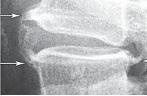

Костные разрастания и высота межпозвонкового промежутка косвенно указывают на процессы, которые происходят в межпозвонковом диске, что подтверждается при сравнении рентгенологических и МРТ обследований.

Рассмотрим серию снимков.

Рентгенограмма № 4

Иллюстрация к книге — Остеохондроз для профессионального пациента [i_068.jpg]